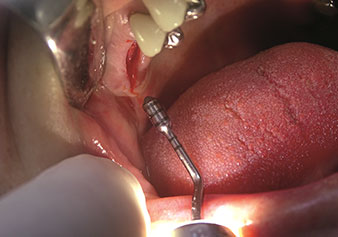

Following preparation of the maxillary sinuses with the corresponding instrument set (Fig. 3), the new Z35P instrument (Fig. 4) is used to lift the membrane hydrodynamically. The same instrument set can also be used for piezosurgical preparation of the implant bed in increasing diameters (Figures 3 and 4 included with the kind permission of Dr Mario Kirste, Frankfurt/Oder).

Another important property of piezoelectric devices, which is an indication for the use of piezo technology, is the possibility of using instruments to redirect the preparation vibrations. The retrograde preparation can be done very elegantly using piezoelectric devices by redirecting the vibration energy within the instrument. The resulting reduced preparation of hard and soft tissue allows smaller accesses and thus reduces perioperative morbidity of patients following apical resection.